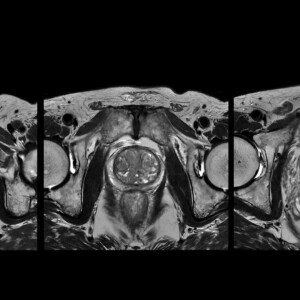

Με την εξέταση αυτή γίνεται η ακριβής απεικόνιση κυρίως του ουρογεννητικού συστήματος (θήλυ/άρρεν) που περιλαμβάνει τα έσω γεννητικά όργανα, την ουροδόχο κύστη, μέρος των ουρητήρων κ.α.

Πρόκειται για μια εξέταση που βοηθά στην διάγνωση, σταδιοποίηση και παρακολούθηση ασθενών με καλοήθη υπερπλασία του προστάτη αδένα ή νεοπλάσματα αυτού. Στην περίπτωση που χρειάζεται η διενέργεια βιοψίας μας βοηθά να εντοπίσουμε ύποπτες περιοχές και η λήψη ιστού να πραγματοποιηθεί με ακρίβεια.